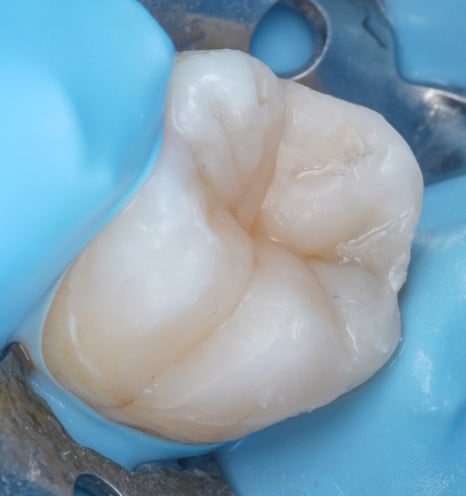

마지막으로 레진으로 치아 형태를 하나하나 만들어갔어요.

해당 치아와 닿는 위쪽 어금니와 해당 치아의 반대쪽 어금니의 형태를 참고하여 실제 환자분의 치아의 형태를 그대로 재현하도록 했습니다.

힘이 한쪽으로 몰리지 않게, 씹을 때 특정 부위만 아프지 않게 교합 조정을 했습니다.

어금니는 하루에도 식사를 하며, 수천 번씩 일을 하는 치아라서 이 과정을 꼼꼼하게 해야 추후 다시 문제가 생기지 않거든요.

심미적으로도 “여기 치료했지~”라는 느낌이 안 들도록 심혈을 기울였어요.

어금니 레진은 씹는 힘을 견딜 수 있는지가 중요해요.

씹는 힘을 고려해 충분히 조정을 한 후에야 모든 과정을 마칠 수 있었는데요.

촬영일 : 251201